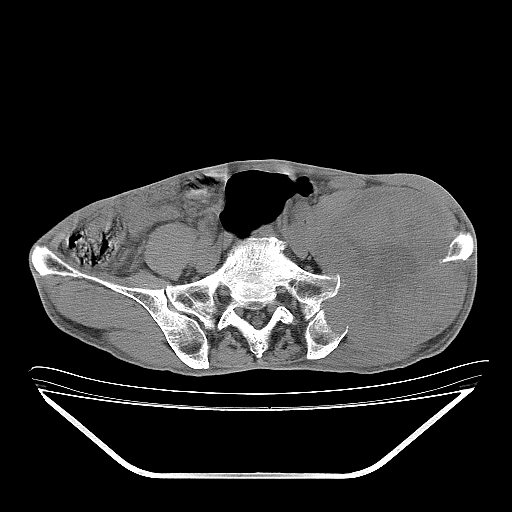

以下是引用天南地北在2007-10-4 18:01:00的发言:[br][br]考虑左髂部恶性肿瘤(溶骨性骨质破坏+软组织肿块影+残留骨质);以滑膜肉瘤可能性大。[br]建议穿刺活检

以下是引用liuyue在2007-10-4 23:38:00的发言:[br]左髂部恶性肿瘤,建议穿刺活检,或先做肺部检查,除外肺癌转移之可能。